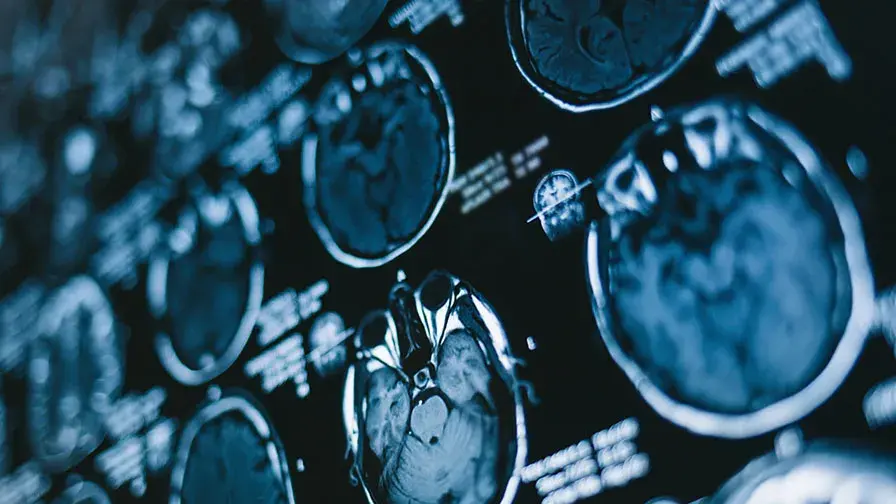

• Définir l'état de conscience du patient est parfois difficile à établir et nécessite à la fois des examens de neuroimagerie et une expertise clinique.